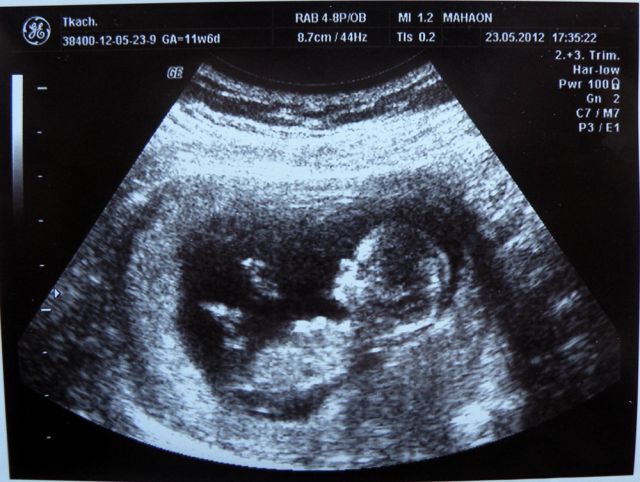

При сроке одиннадцать недель размер плода составляет около 6 см. Плод на 11-й неделе весит почти

Закладывается цвет радужной оболочки глаз. Формируется хватательный рефлекс. На УЗИ можно заметить, как малыш пытается что-то схватить ручкой.

При сроке 11 недель размер плода тем заметнее, что он начинает распрямляться. Красавцем его еще не назовешь, но плод все больше начинает напоминать ребенка своими очертаниями и функциями органов.

К одиннадцатой неделе половые органы уже сформированы. Начинают работать почки и кишечник плода. Малыш во чреве мамы шевелится уже очень активно, но он пока слишком мал, чтобы мать могла заметить его движения. Но уже очень скоро она ощутит первые толчки изнутри.

УЗИ на 11 неделе беременности